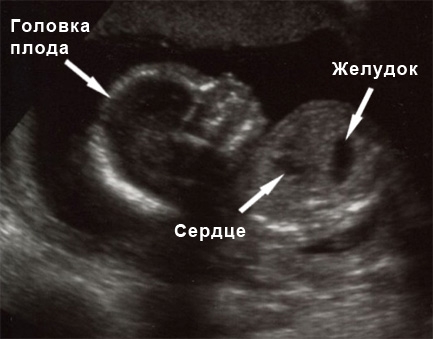

Пришло время для одного из самых значимых ультразвуковых исследований. На двенадцатой неделе беременности УЗИ становится обязательным этапом диагностики. В ходе обследования помимо измерения размеров плода, проводятся замеры головы, плечевых, локтевых, бедренных, лучевых, большеберцовых и малоберцовых костей. Также оценивается симметрия конечностей и их двигательная активность, а также правильное расположение сердца и желудка. На этом сроке с высокой вероятностью можно выявить возможные пороки сердца. Важно измерить толщину воротниковой зоны, которая в норме не должна превышать 2.5 миллиметров; превышение этого значения может указывать на риск хромосомных аномалий, таких как синдром Дауна. Врач также внимательно изучает носовые кости плода, так как у детей с синдромом Дауна они, как правило, короче. Это связано с тем, что формирование носовых костей при данной патологии завершается значительно позже, чем у здоровых плодов. Таким образом, визуализация носовых костей на УЗИ на двенадцатой неделе является важным диагностическим показателем.